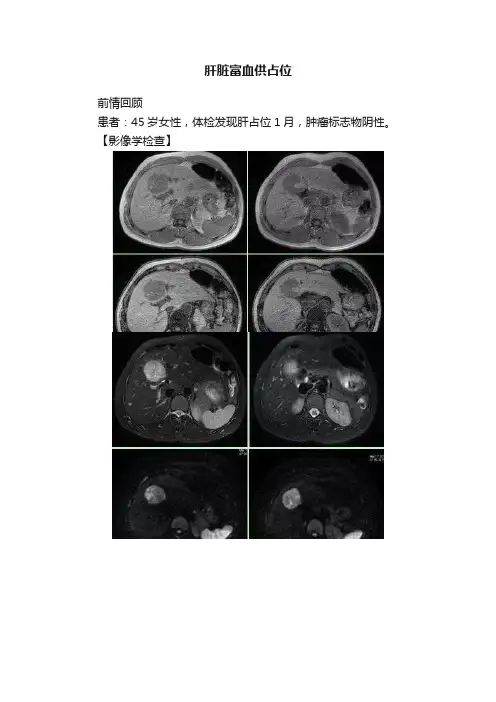

肝脏富血供占位前情回顾患者:45岁女性,体检发现肝占位1月,肿瘤标志物阴性。

【影像学检查】【本例影像表现】 MRI :肝左右叶交界处可见肿块,边界尚清。

T1WI 同反相位呈混杂信号,以低信号为主,局部可见点状及片状高信号,反相位未见信号减低区;T2WI 呈混杂信号,以中高信号为主,局部可见更高信号影;DWI呈高信号;蒙片呈混杂低信号伴高信号区;增明扫描动脉期明显不均匀强化,门脉期及延迟期强化程度减低但仍高于周围肝实质,肿物内可见始终未强化的不规则区域。

CT:肝左右叶交接区可见肿块,边界尚清。

平扫呈混杂低密度,增强扫描动脉期呈明显不均匀强化,门脉期及延迟期可见强化程度减低,内部可见始终不强化区。